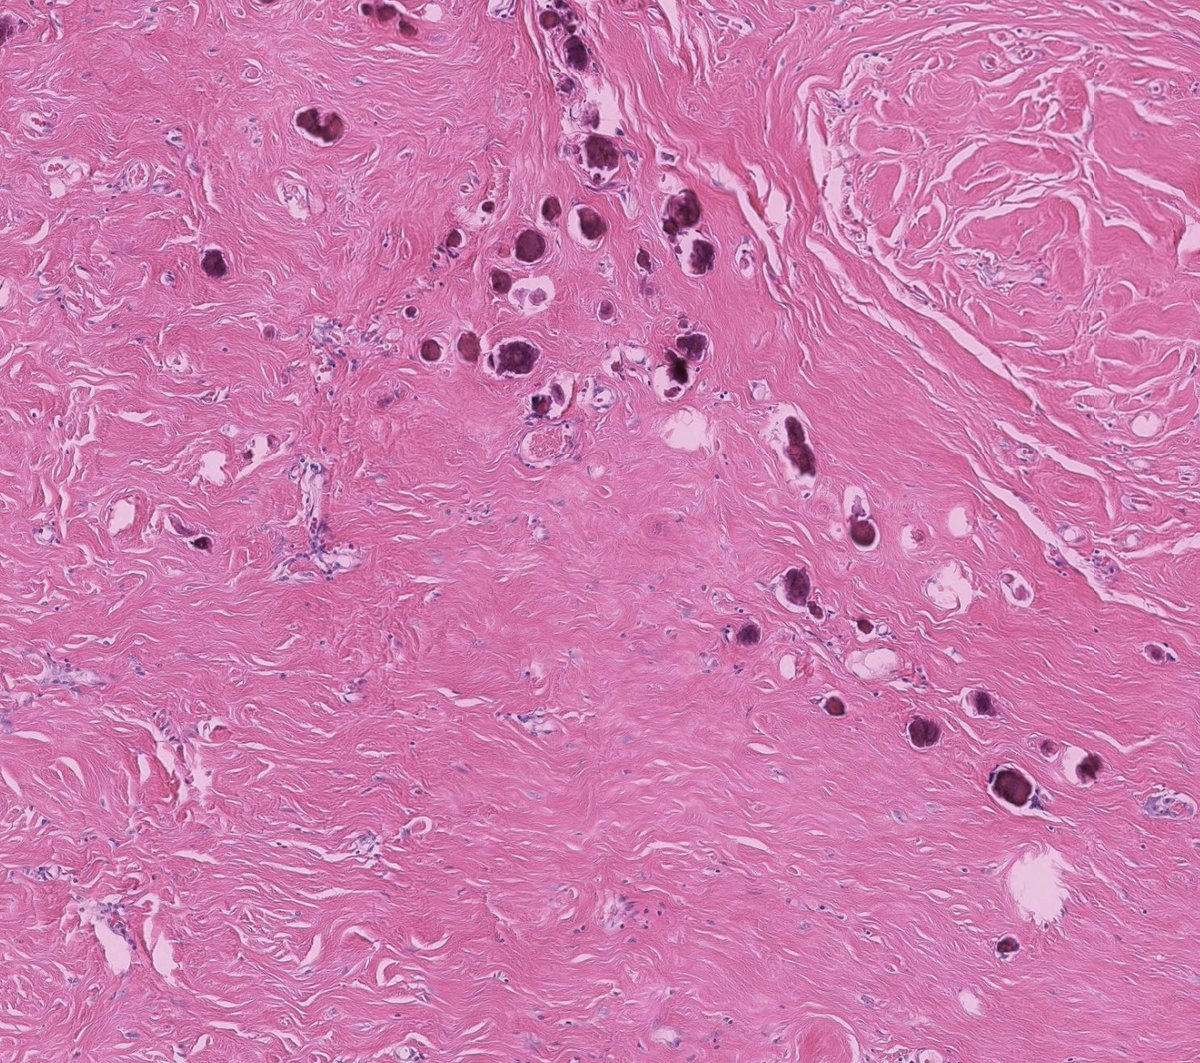

Couldn't be more excited to announce the launch of pathlibrary.com, the virtual slide site I wish had existed during my pathology residency. You can:

- See annotated histologic features